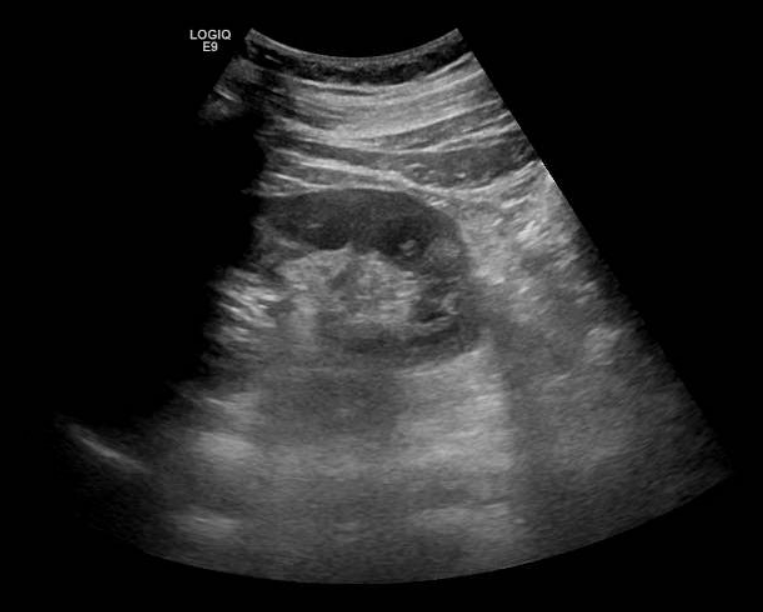

Se solicita ecografía abdominal que muestra líquido en espacio pararrenal posterior derecho bajo, sobre músculo psoasilíaco derecho, y leve ectasia piélica derecha sin identificar causa.

Entre las entidades que afectan al espacio pararrenal nos encontramos linfangioma, entidades fibróticas, hematomas, abscesos, neoplasias… Por tanto, se completa estudio con TAC abdominal con contraste. En el TAC se observa litiasis de 3 mm en meato ureteral derecho con dilatación pielocalicial grado II y leve-moderada cantidad de líquido en espacios retroperitoneales peri y pararrenal derechos, que se relacionan con salida de contraste intravenoso en fase excretora, compatible con rotura de la vía urinaria sin identificarse claro punto de fuga.

Entre las indicaciones de ecografía, se encuentra el dolor abdominal sugestivo de cólico nefrítico en pacientes que no responden a analgesia. La nefrolitiasis es un hallazgo ecográfico muy frecuente en la exploración ecográfica renal y puede acompañarse de dilatación o no de la vía urinaria u otras complicaciones que nos orientarán en el manejo del paciente.